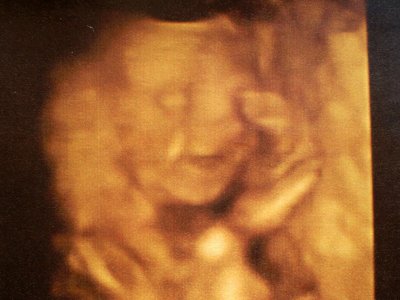

Monka igen, azt hiszem elég nagy szerencsém van anyósomékkal, remélem így is marad a viszony. Nem hiszem hogy lesz még egyszer ilyen mázlim, mármint mosolygós babót látni pocakban, de ki tudja. Megosztom azért veletek a képet, ha nem baj. A 21. hétben volt a 4d. És kint is különben egy állandóan vigyorgó kiscsaj.

Kép